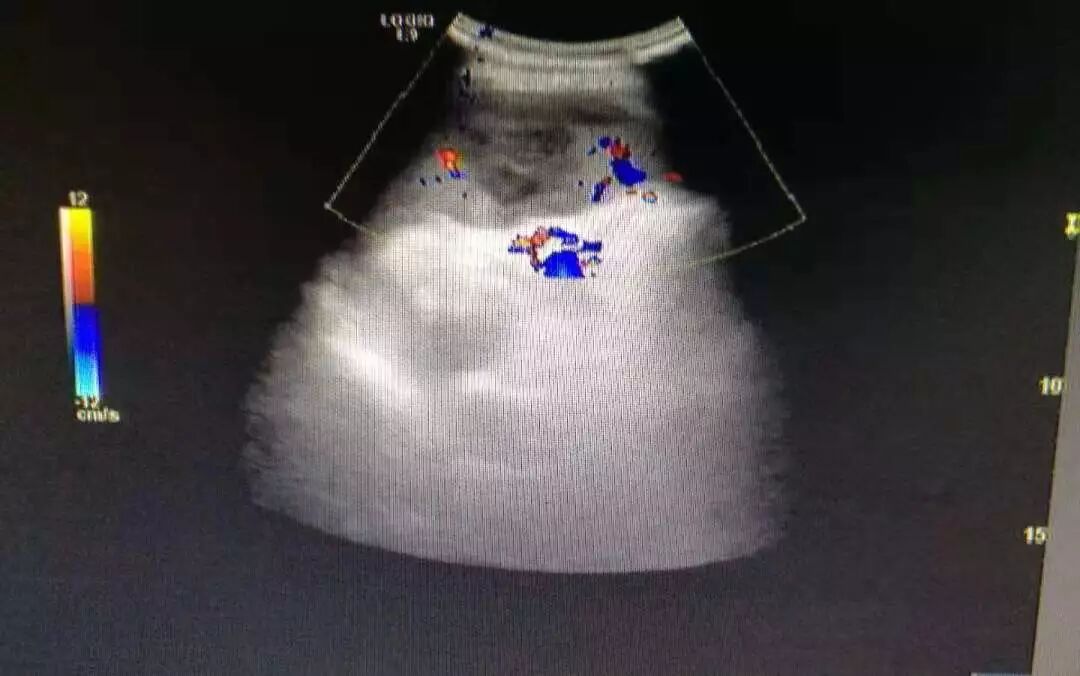

发现左上腹疼痛时,首选超声,CT检查。超声检查简便,时间短,能及时发现脾脏内病变,脾梗死超声表现呈棱形病灶,回声减低,当缺血坏死区扩大时,内可见不规则无回声区,超声彩色多普勒显示病灶区内无血流灌注。此患者经超声确诊过后,及时转上级医院做干预治疗,目前病情稳定。